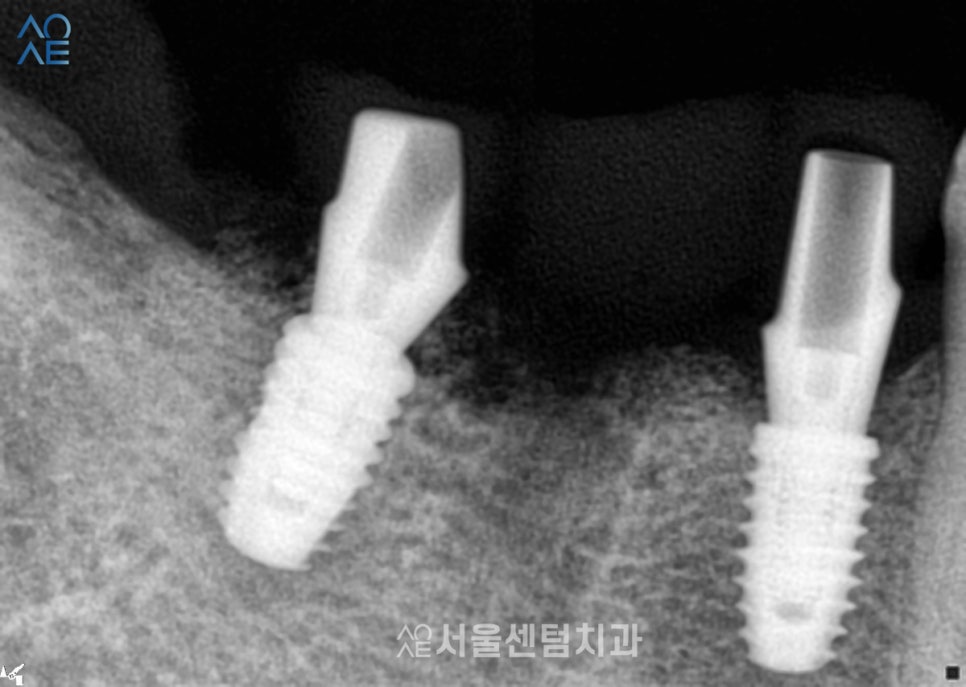

20대임플란트 수술한 부위가

잘 아물 때까지 기다리는 동안에

환자분이 원하셨던 앞니 치료도 진행했습니다.

기존 충전 재료를 모두 제거하고

새롭게 생긴 2차 충치를 치료하였습니다.

이후에 지르코니아 보철물도 수복하고요.

임플란트수술 경과도

꾸준히 잘 체크했습니다^^

첫 임플란트를 수술하고 나서

원래는 많이 내원할 필요는 없지만

이 환자분의 경우엔 추가 치료가 있다보니

임플란트 크라운을 올리기까지

9번 정도를 내원했던 것 같습니다.

덕분에 경과 체크도 꼼꼼하게 할 수 있었고

크라운도 잘 제작하여 수복해드렸습니다.